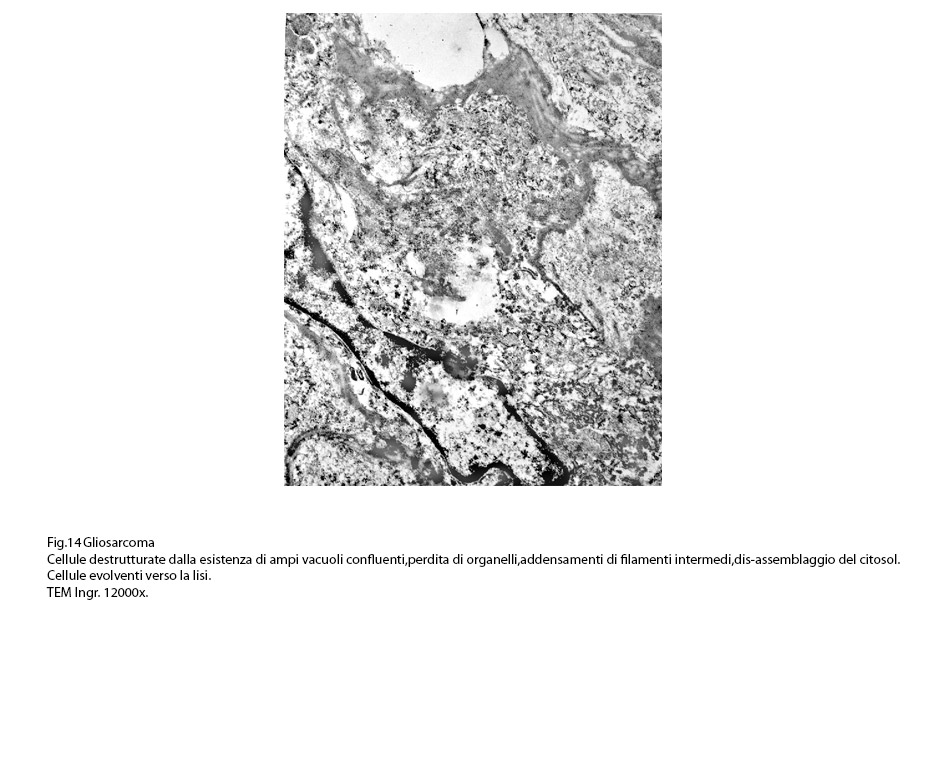

Fig.13  Fig.14

Fig.14